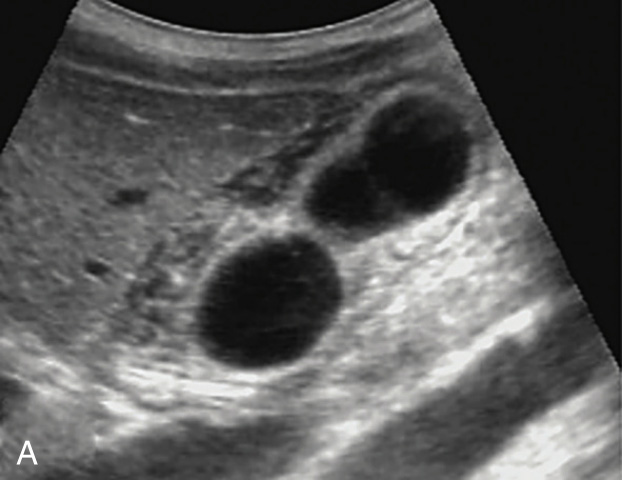

1)胆囊增大,胆囊壁弥漫性增厚,不光滑,呈“双边征”,胆囊壁内可见较丰富血流信号(图2-2-1)。

图2-2-1 急性胆囊炎常规超声图像

A.胆囊壁弥漫性明显增厚,不光滑,呈“双边征”;B.胆囊壁内较丰富的血流信号